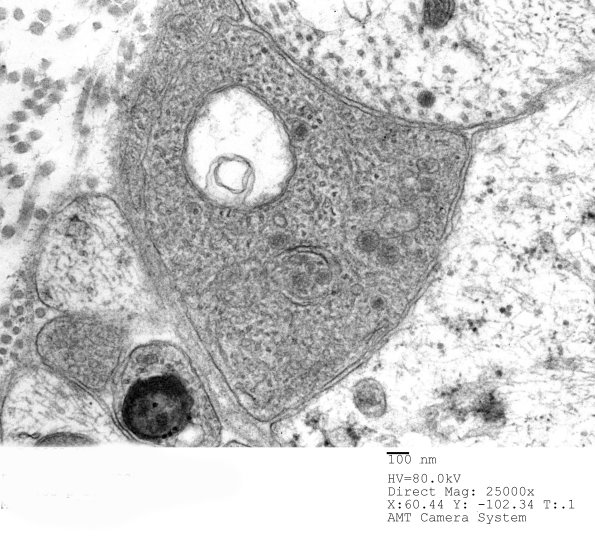

Higher magnification of image 3B11A. (electron micrographs)